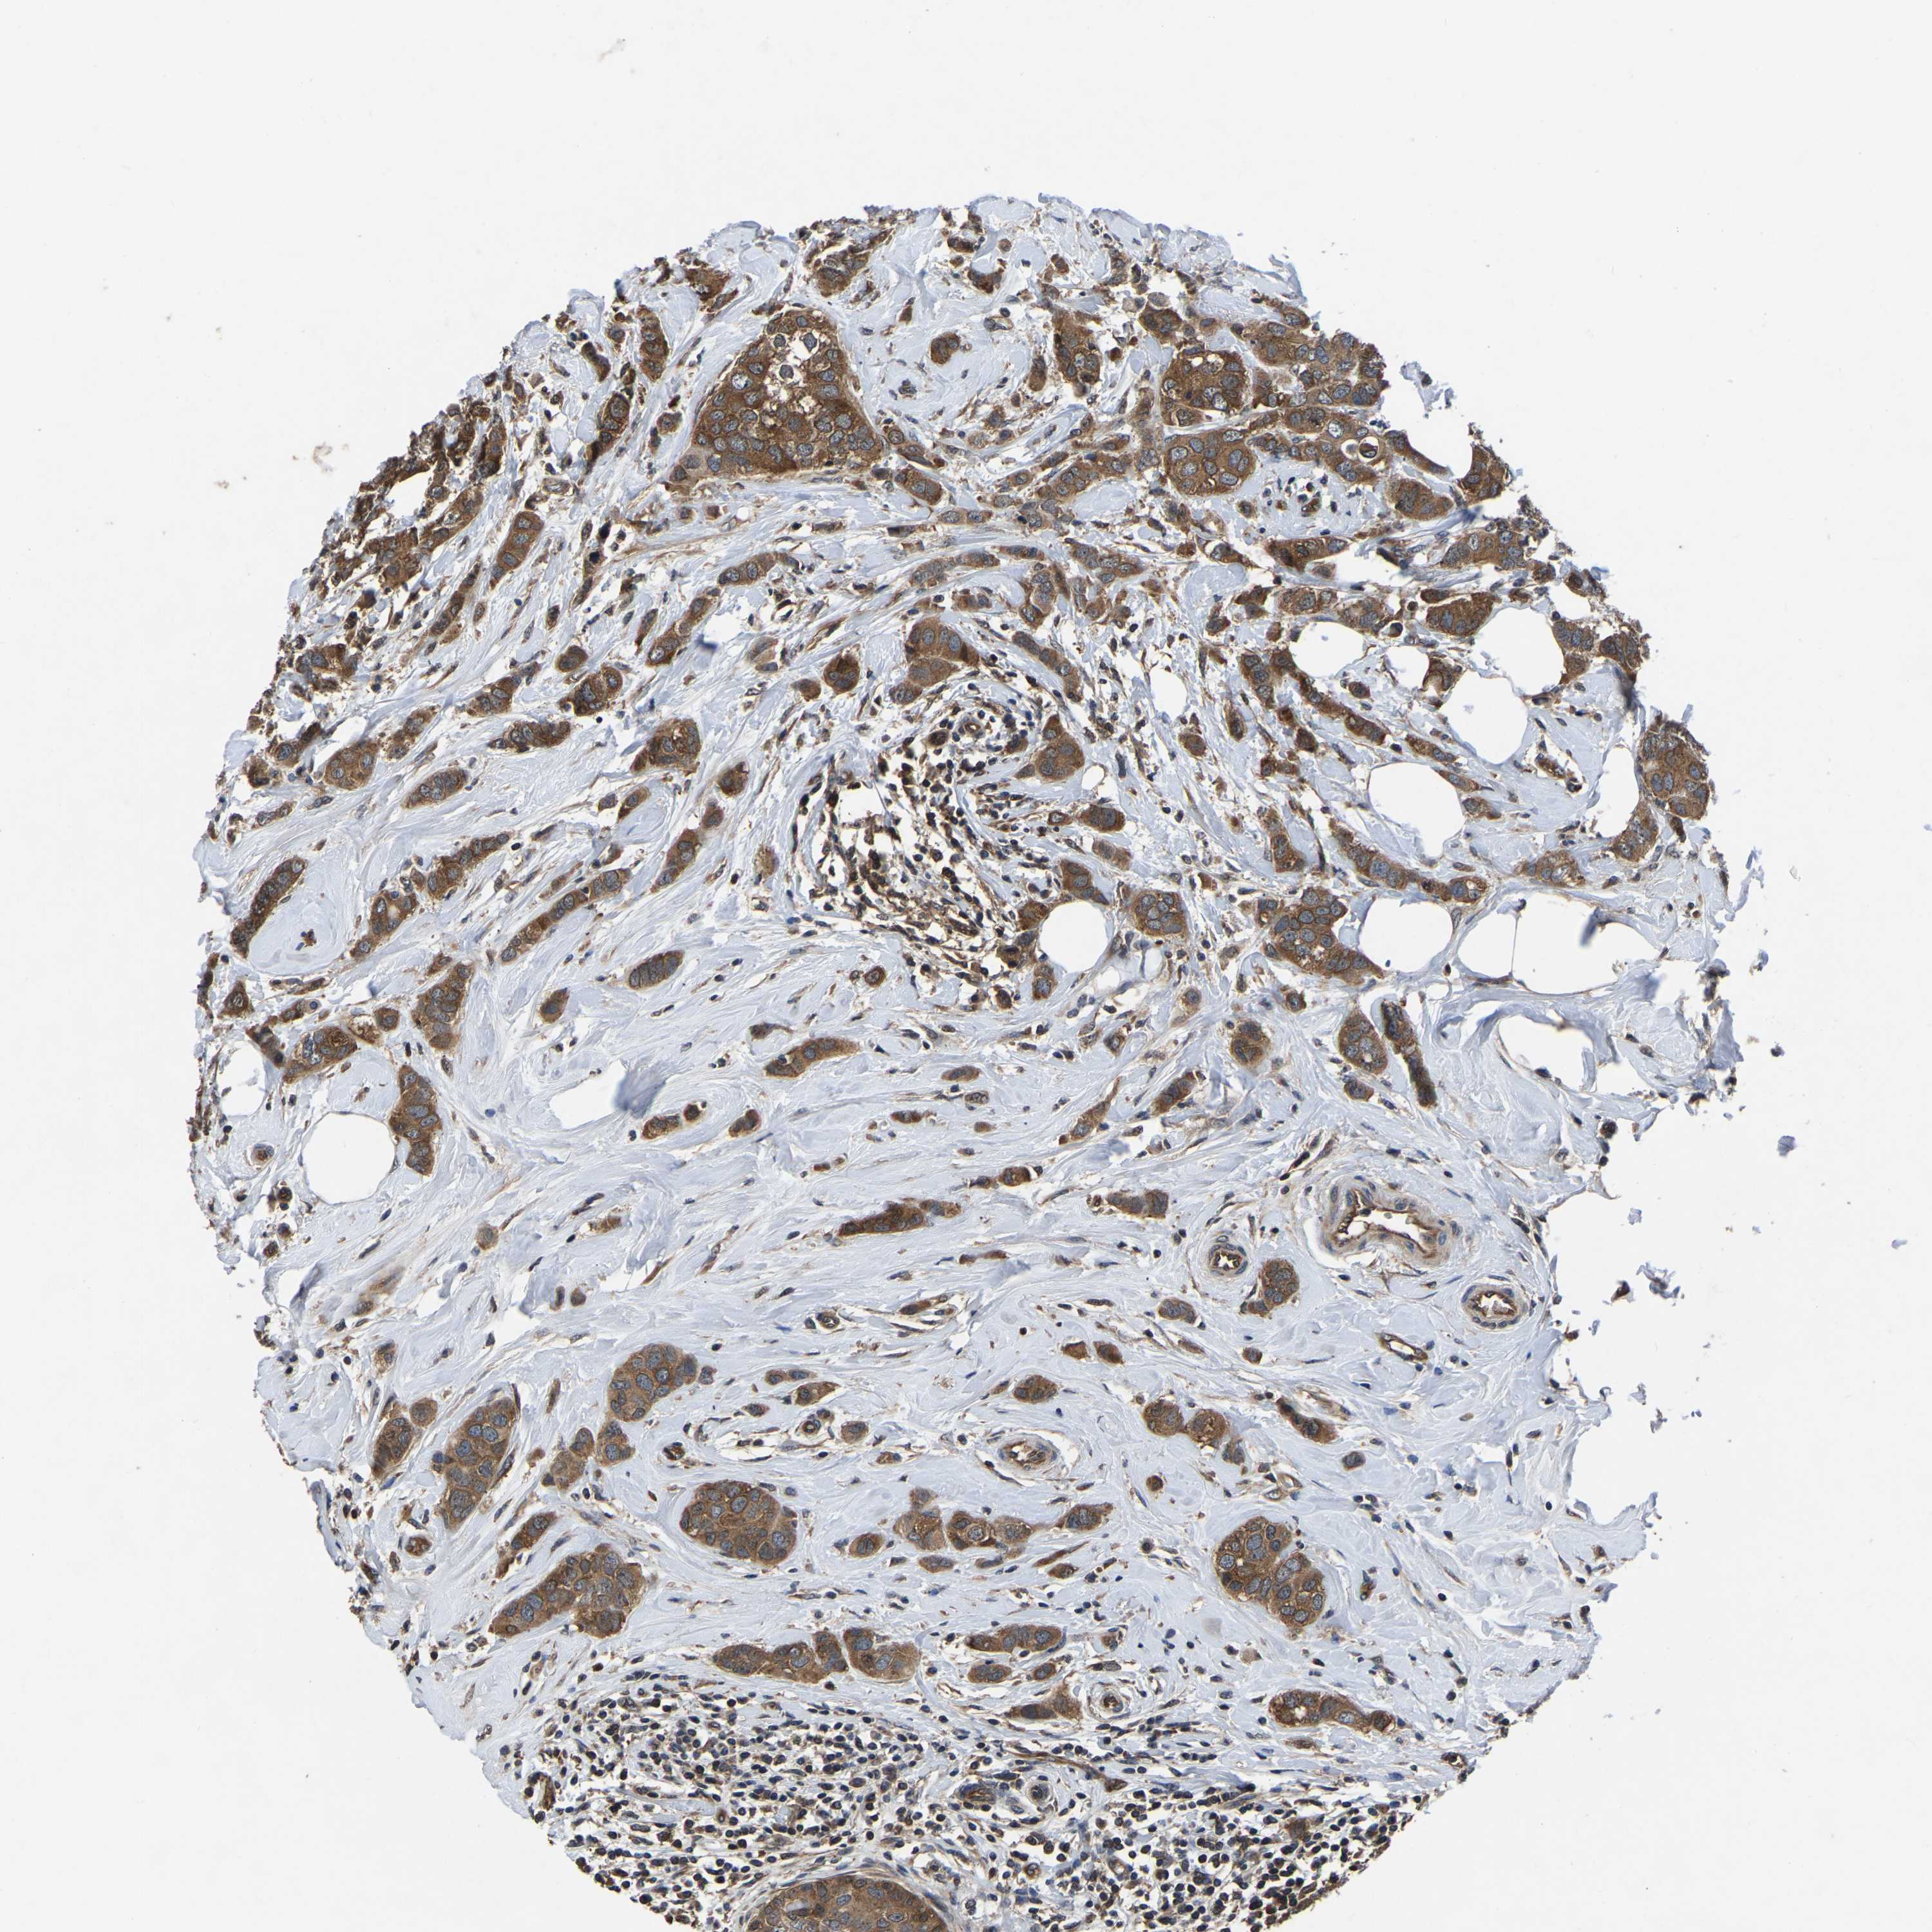

CANCER BREAST CANCER Show tissue menu

BRCA TCGA BRCA VALIDATION PROTEIN EXPRESSION

ANTIBODIES

AND

VALIDATION